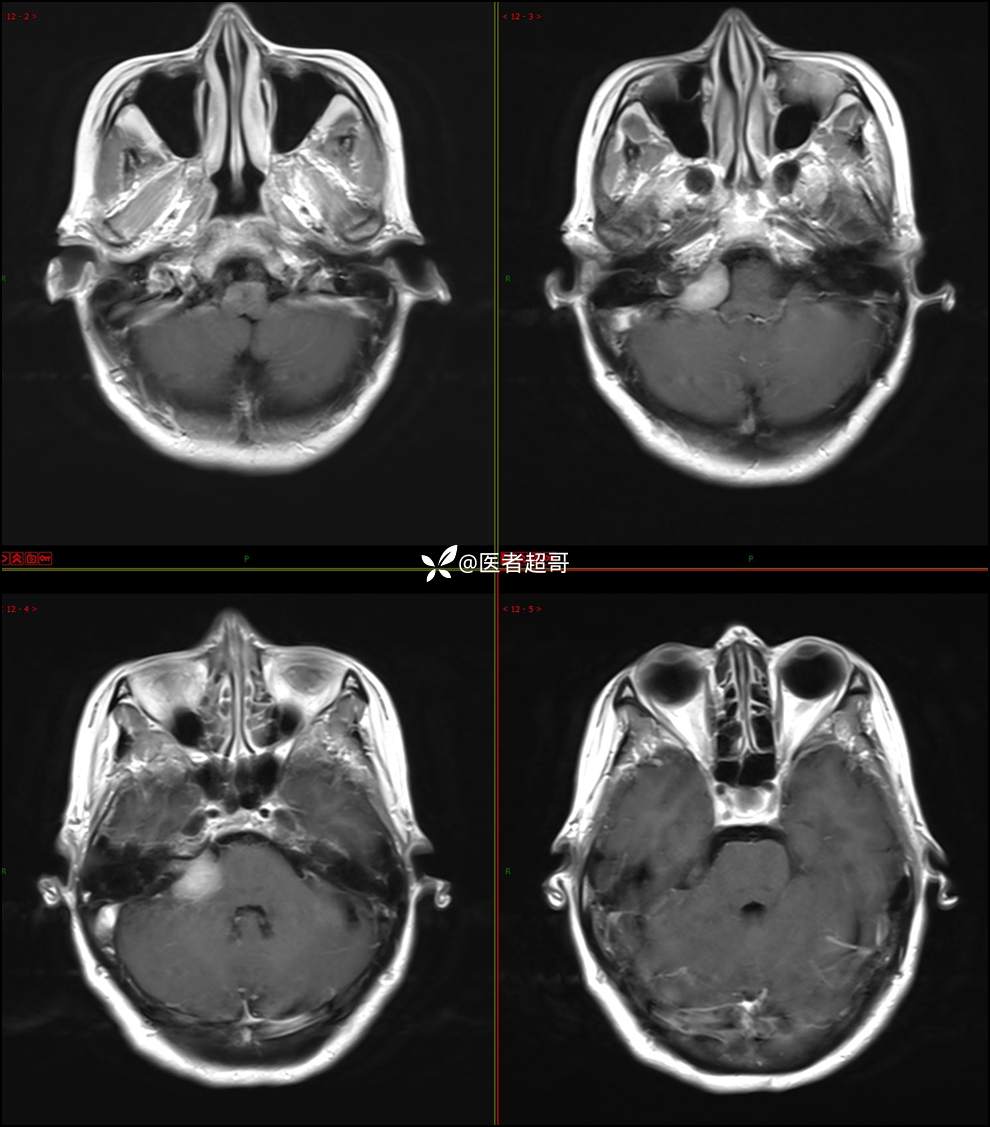

CPA区占位,是鞘瘤?脑膜瘤?请赏析!

现病史:患者3年前出现耳鸣,蝉鸣音,反复发作,夜间自觉明显,于2018年8月至我院耳鼻喉科就诊,行颅脑CT检查未发现明显异常改变,给予对症处理(具体不详);4天前突发头晕,伴明显恶心,至市人民医院就诊,行颅脑CT未见明显异常,颅脑MRI发现右侧桥脑小脑角区占位性病变。本次发病来无明显头痛,无肢体抽动,无大小便失禁。为求进一步诊治,遂来我院门诊,以“听神经良性肿瘤”收住入院。发病来,患者神志清,精神可,二便正常,饮食可,睡眠不佳,近期体重无明显变化,否认癫痫发作病史。